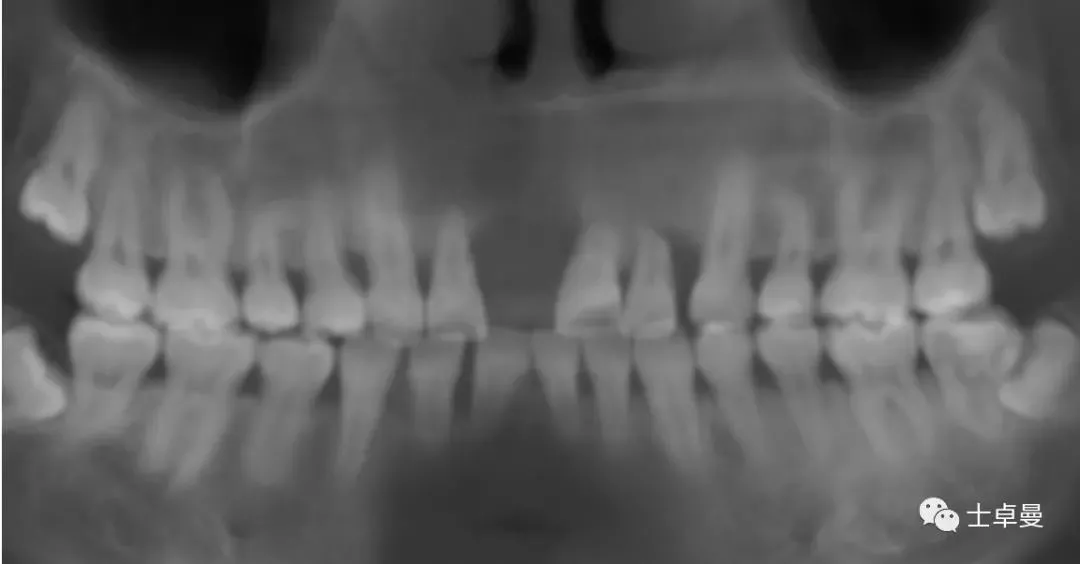

影像学检查

·      CBCT显示11可用骨高度13.3mm,宽度6.9mm;

·      12近中牙槽嵴吸收至根尖1/3处,远中牙槽嵴吸收至根1/2处;

·      21可见根吸收影相,近中牙槽嵴吸收至根尖1/3处;

·      22牙槽嵴近中吸收至根1/3处,远中吸收至根尖。